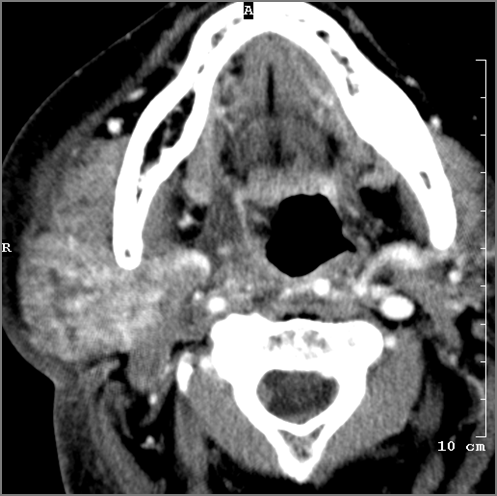

9 month old male presenting to the emergency room with poor feeding, fever, respiratory distress and possible retropharyngeal abscess or suppurative retropharyngeal adenitis.Exam

| Nasopharynx | Correct Answer | Your Answer |

|---|---|---|

There is excessive enhancement or thickening of the mucosa or hypertrophy of the lymphoid tissue in the nasopharynx. |

Yes | NA |

There is evidence of an abscess within the lymphoid tissue of the nasopharynx. |

No | NA |

There is edema within the fat of the adjacent parapharyngeal space. |

There is an abscess within the fat of the adjacent parapharyngeal space. |

There is edema within the fat of the adjacent retropharyngeal space. |

There is an abscess within the fat of the adjacent retropharyngeal space. |

| Oropharynx | Correct Answer | Your Answer |

There is excessive enhancement or thickening of the mucosa or hypertrophy of the palatine or lingual tonsillar tissue or the lymphoid tissue along the glossotonsillar sulci and posterior pharyngeal wall. |

Impression

Expert Answer

Pharyngitis with suppurative retropharyngeal adenitis.